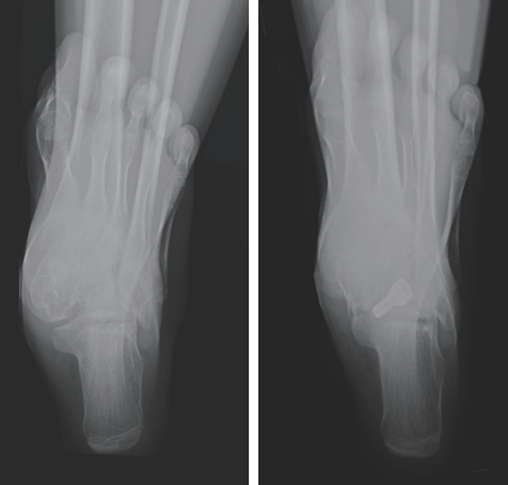

图14:跟骨轴位X光片,右侧为术后,跟骨外翻已纠正。